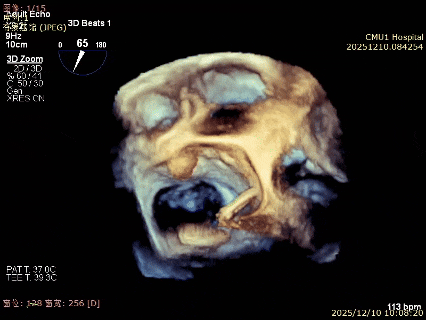

术前3D

术前3Dcolor

3D-TEE二尖瓣相关解剖学参数:后叶长度:22-25mm,前叶长度:31-34mm;瓣环AP径:47mm,ML径:48mm;瓣口面积:约7.8cm²;脱垂宽度:30mm,最大连枷间距:14mm。

术前即刻TEE进一步明确了二尖瓣反流的机制(DMR)及反流程度(5+),重点完善了病变区域二尖瓣解剖结构的评估,预估手术难点/影响手术效果的解剖结构为冗长的二尖瓣后叶(PML约25mm),宽大的脱垂(Flail Width约30mm),超大的连枷间距(Flail gap约14mm)。